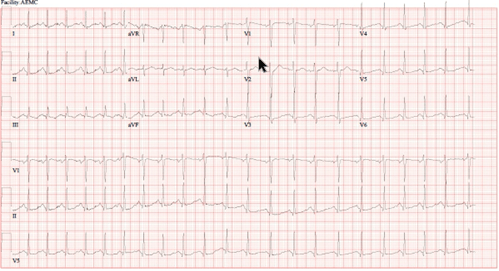

A 25-year-old female presented to the ED after overdosing on ecstasy. In the ED, she was tachycardic with a rate of 132, and her temperature was 37.2 degrees Celsius . On physical examination, she appeared somewhat disheveled but was alert and oriented. Her pupils were dilated 5-6 millimeters bilaterally. No notable clonus, asterixis, rigidity of extremities, or diaphoresis was evident. An electrocardiogram was performed which showed sinus tachycardia with a rate of 132 beats per minute (Figure 1). Her laboratory analyses were unremarkable, and urine drug screen was positive for methamphetamine and cannabinoids. Treatment interventions in the ED included 1,000 mL of isotonic crystalloid fluids and 2 mg of IV lorazepam for agitation. The toxicology service was consulted, and the patient was admitted to the general medical floor (GMF). While in GMF around 2 AM, the patient became tachycardic to a heart rate of 200 and severely agitated. She was given 5 mg IM haloperidol and required 2 doses of 5 mg IV diazepam at 2 AM and 7 AM. At around 8 AM, the patient seemed to have returned to her baseline mental status but remained mildly somnolent. She admitted to taking pills to harm herself. No persistent signs of sympathomimetic toxidrome or hyponatremia were noted, and her heart rate was now 90-100. The patient was then evaluated by psychiatry. At the time of psychiatric evaluation, she no longer endorsed suicidal ideations and was thus cleared from a psychiatric standpoint. The patient was adamant about leaving the hospital at this time. However, her creatinine kinase was 9244 IU/L, and she was somnolent earlier that day. The psychiatry team was unable to convince the patient to stay for further observation. She proceeded to leave against medical advice.

Figure 2: EKG showing sinus tachycardia with a rate of 132 but no evidence of acute ischemic changes or QT prolongation